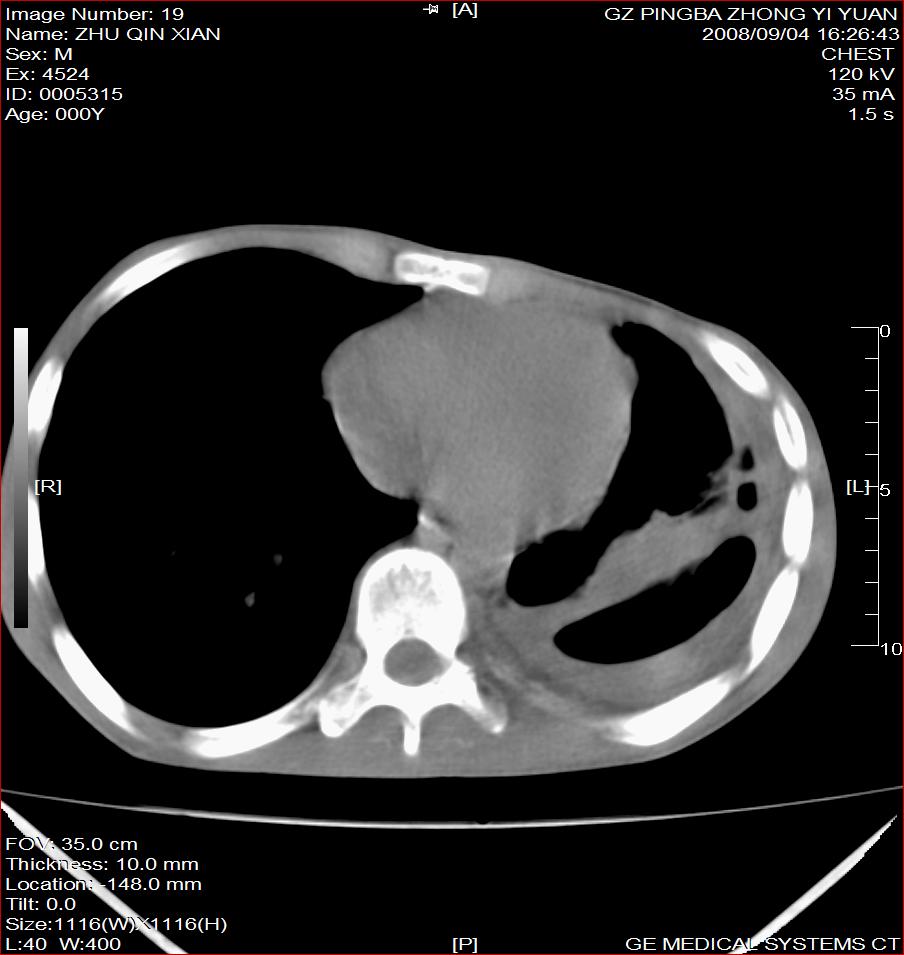

以下是引用随光逐影在2008-9-4 20:05:00的发言:[br]1)考虑两肺结核。2)左侧胸膜炎(胸膜肥厚、粘连,胸腔积液)。3)左侧局限性气胸。

以下是引用子十在2008-9-4 19:34:00的发言:[br]左上肺结核并空洞及双肺播散。节段性肺不张、胸腔积液、胸膜肥厚粘连。[br]